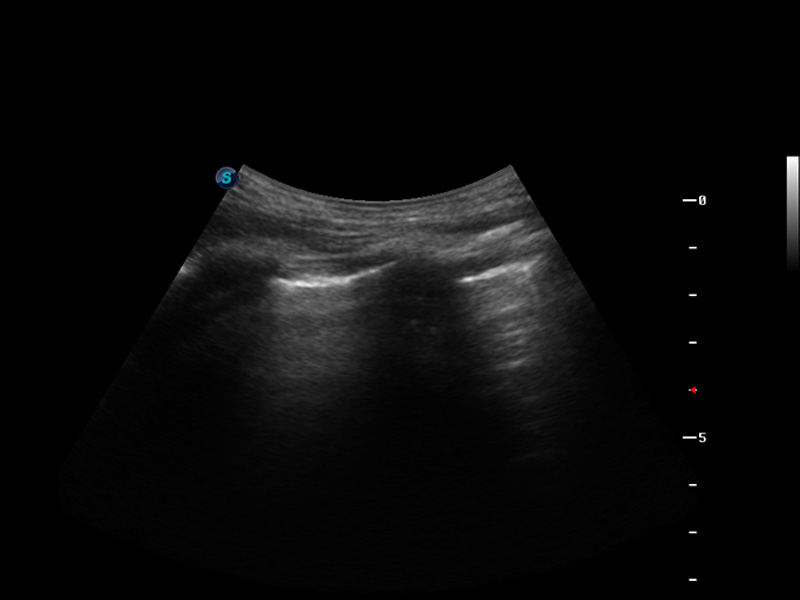

S9便携式彩色多普勒超声诊断仪是美狮贵宾会官网研发的高端便携彩超设备,外观设计新颖、产品性能卓越。S9在便携超声领域采用了突破传统的触摸屏交互设计,并以先进的软件硬件技术和设计理念,为您带来清晰的图像质量、稳定的工作性能和便捷的操作体验。